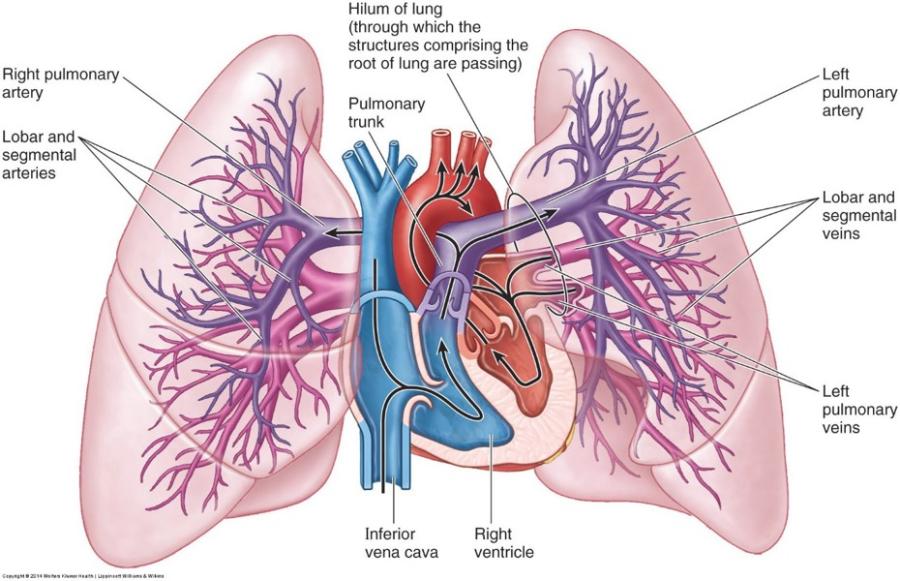

pulmonary circulation: how many pulmonary veins are there?

show the pulmonary trunk, 2 pulmonary arteries and 4 pulmonary veins in the picture?

4....2 on the right and 2 on the left

big blue tube in middle is the pulmonary trunk...two blue pathways going in either direction from this are your right and left pulmonary arteries...then you can see the 4 little red vessels coming in from the sides going back to the heart (pulmonary veins)

briefly summarize the pulmonary circulation

- Deoxygenated blood from your body enters the right atrium of your heart through the superior vena cava and the inferior vena cava.

- From the right atrium, the deoxygenated blood drains into the right ventricle

- The right ventricle then contracts, forcing the deoxygenated blood through the pulmonary semilunar valve up top and into the pulmonary artery

- The pulmonary artery carries the blood that’s very low in oxygen to the lungs, where it becomes oxygenated.

- Freshly oxygenated blood returns from the lungs to the left atrium of the heart via the pulmonary veins...then goes into left ventricle to them get pumped to the peripheries

notice the hilum of the lungs and the pulmonary trunk and the superior and inferior vena cava and the aortic arch